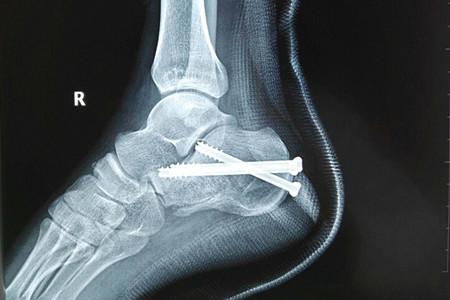

跟骨骨折以足跟部劇烈疼痛,腫脹和淤斑明顯,足跟不能著地行走,跟骨壓痛為主要表現(xiàn)。本病成年人較多發(fā)生,常由高處墜下或擠壓致傷。經(jīng)常伴有脊椎骨折,骨盆骨折,頭、胸、腹傷。跟骨為松質(zhì)骨,血循供應(yīng)比較豐富,骨不連者少見。但如骨折線進(jìn)入關(guān)節(jié)面或復(fù)位不良,后遺創(chuàng)傷性關(guān)節(jié)炎及跟骨負(fù)重時(shí)疼痛者很常見。